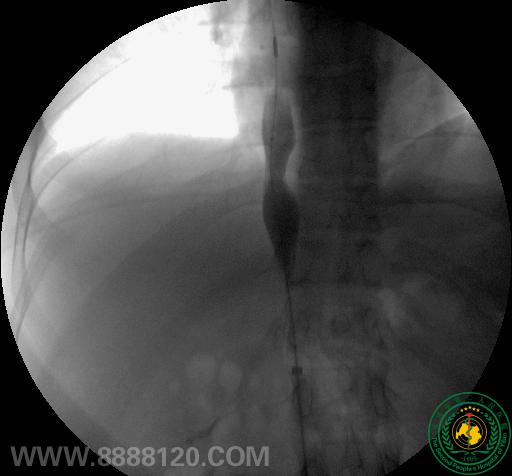

影像科介入室近日完成一例布加氏综合征介入治疗

影像科介入室近日完成一例布加氏综合征介入治疗2451